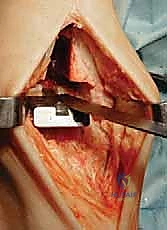

4. تركيب المفصل الصناعي (Implantation)

يتكون مفصل الكاحل الصناعي الحديث عادة من ثلاثة أجزاء:

* قطعة معدنية علوية: تُثبت في عظمة الظنبوب (الساق).

* قطعة معدنية سفلية: تُثبت في عظمة الكاحل.

* قطعة بلاستيكية (بولي إيثيلين عالي الكثافة): توضع بين القطعتين المعدنيتين لتنزلق بسلاسة وتمتص الصدمات، محاكيةً وظيفة الغضروف الطبيعي.

يتم تثبيت هذه الأجزاء بإحكام (إما عن طريق الضغط المباشر لتشجيع نمو العظم حولها، أو باستخدام أسمنت طبي خاص).